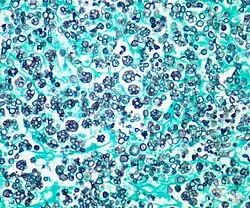

Histologic stain of a Prototheca zopfii infection in a dog | |

Protothecosis, otherwise known as Algaemia, is a disease found in dogs, cats, cattle, and humans caused by a type of green alga known as Prototheca that lacks chlorophyll and enters the human or animal bloodstream. It and its close relative Helicosporidium are unusual in that they are actually green algae that have become parasites.[1] The two most common species are Prototheca wickerhamii and Prototheca zopfii. Both are known to cause disease in dogs, while most human cases are caused by P. wickerhami.[2] Prototheca is found worldwide in sewage and soil. Infection is rare despite high exposure, and can be related to a defective immune system.[3] In dogs, females and Collies are most commonly affected.[4]

Disseminated protothecosis is most commonly seen in dogs. The algae enters the body through the mouth or nose and causes infection in the intestines. From there it can spread to the eye, brain, and kidneys. Symptoms can include diarrhea, weight loss, weakness, inflammation of the eye (uveitis), retinal detachment, ataxia, and seizures.[11]

Dogs with acute blindness and diarrhea that develop exudative retinal detachment should be assessed for protothecosis.[6] Diagnosis is through culture or finding the organism in a biopsy, cerebrospinal fluid, vitreous humour, or urine. Treatment of the disseminated form in dogs is very difficult, although use of antifungal medication has been successful in a few cases.[4] Prognosis for cutaneous protothecosis is guarded and depends on the surgical options. Prognosis for the disseminated form is grave. This may be due to delayed recognition and treatment.[3]